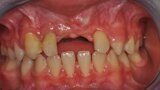

Ryc. 1_Stan miejscowy przed ekstrakcja zębów 11 i 21.